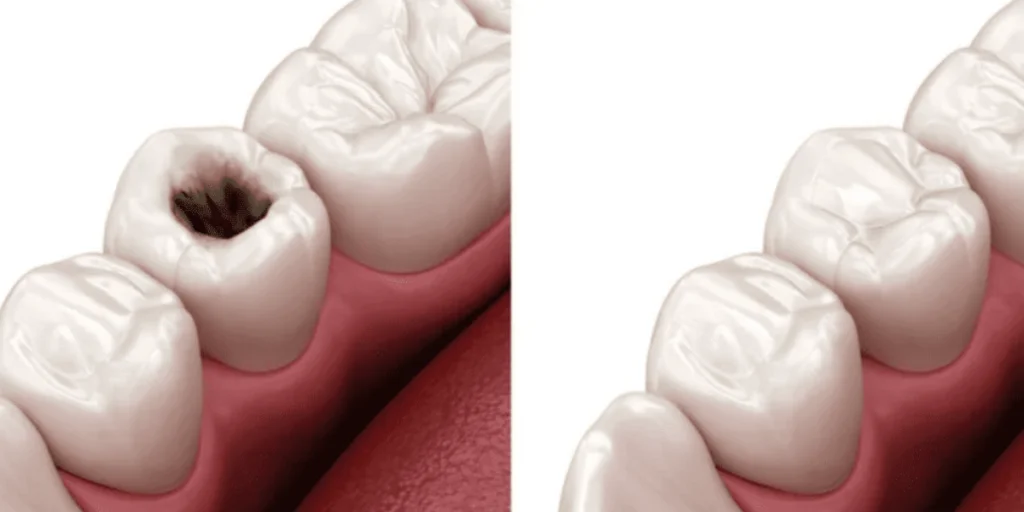

Teeth fillings are materials used by dentists to repair cavities or damage in a tooth. When a tooth develops a cavity due to decay, the dentist removes the decayed part and fills the empty space with a dental filling. Fillings help restore the strength, shape, and function of the tooth, preventing further damage.

Why Do You Need a Teeth Filling?

A tooth filling is necessary when you have:

- Cavities caused by bacteria and plaque buildup

- Cracks or fractures in a tooth due to injury

- Worn-out teeth from grinding or chewing hard foods

- Sensitivity or pain due to enamel erosion

If left untreated, a damaged or decayed tooth can worsen, leading to infections, abscesses, or even tooth loss.